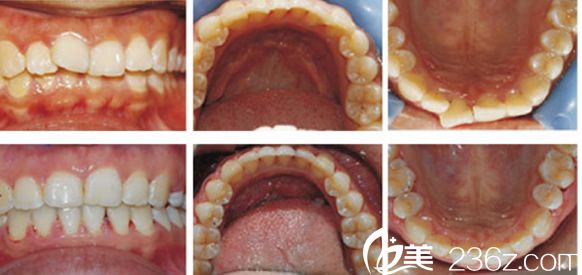

合肥壹加壹牙齿矫正案例恢复过程图: